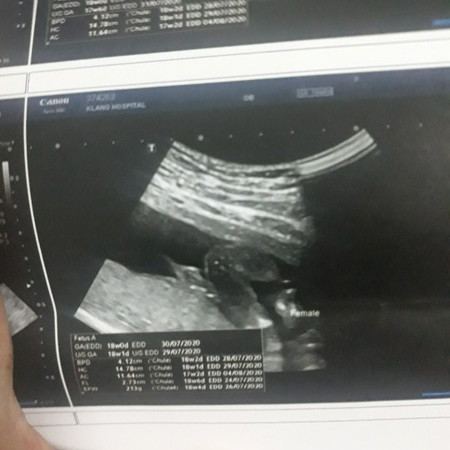

แม่ๆช่วยบอกทีคะว่าผู้ชายหรือผู้หญิงเพราะน้องให้เห็นแค่แปปเดียวเองหมอก็ไม่แน่ใจเหมือนกัน

Femaleแปลว่าผุ้หญิงค่ะ